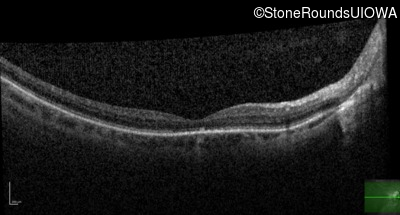

Optical Coherence Tomography - Left - 20/32

Exemplar / OCT Stack

OCT Stack